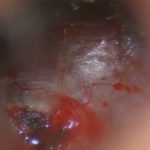

No.’24_69 手術前1

No.’24_69 摘出 前

No.’24_69  摘出 中

No.’24_69 摘出 後